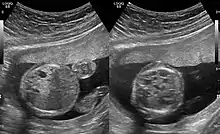

CPAMs are often identified during routine prenatal ultrasonography. Identifying characteristics on the sonogram include: an echogenic (bright) mass appearing in the chest of the fetus, displacement of the heart from its normal position, a flat or everted (pushed downward) diaphragm, or the absence of visible lung tissue.

CPAMs are classified into three different types based largely on their gross appearance. Type I has a large (>2 cm) multiloculated cysts. Type II has smaller uniform cysts. Type III is not grossly cystic, referred to as the "adenomatoid" type. Microscopically, the lesions are not true cysts, but communicate with the surrounding parenchyma. Some lesions have an abnormal connection to a blood vessel from an aorta and are referred to as "hybrid lesions."

The earliest point at which a CPAM can be detected is by prenatal ultrasound. The classic description is of an echogenic lung mass that gradually disappears over subsequent ultrasounds. The disappearance is due to the malformation becoming filled with fluid over the course of the gestation, allowing the ultrasound waves to penetrate it more easily and rendering it invisible on sonographic imaging. When a CPAM is rapidly growing, either solid or with a dominant cyst, they have a higher incidence of developing venous outflow obstruction, cardiac failure and ultimately hydrops fetalis. If hydrops is not present, the fetus has a 95% chance of survival. When hydrops is present, risk of fetal demise is much greater without in utero surgery to correct the pathophysiology. The greatest period of growth is during the end of the second trimester, between 20–26 weeks.

A measure of mass volume divided by head circumference, termed cystic adenomatoid malformation volume ratio (CVR) has been developed to predict the risk of hydrops. The lung mass volume is determined using the formula (length × width × anteroposterior diameter ÷ 2), divided by head circumference. With a CVR greater than 1.6 being considered high risk. Fetuses with a CVR less than 1.6 and without a dominant cyst have less than a 3% risk of hydrops. After delivery, if the patient is symptomatic, resection is mandated. If the infant is asymptomatic, the need for resection is a subject of debate, though it is usually recommended. Development of recurrent infections, rhabdomyosarcoma, adenocarcinomas in situ within the lung malformation have been reported.[4]